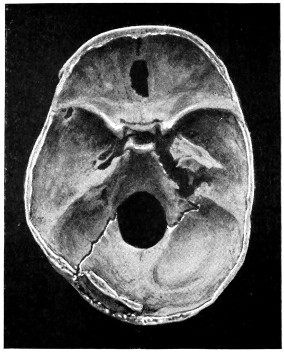

29 A and B. The base of the skull and the base as seen on transillumination 70, 71

50 A and B. The inner aspect of the skull and the same seen on transillumination 137